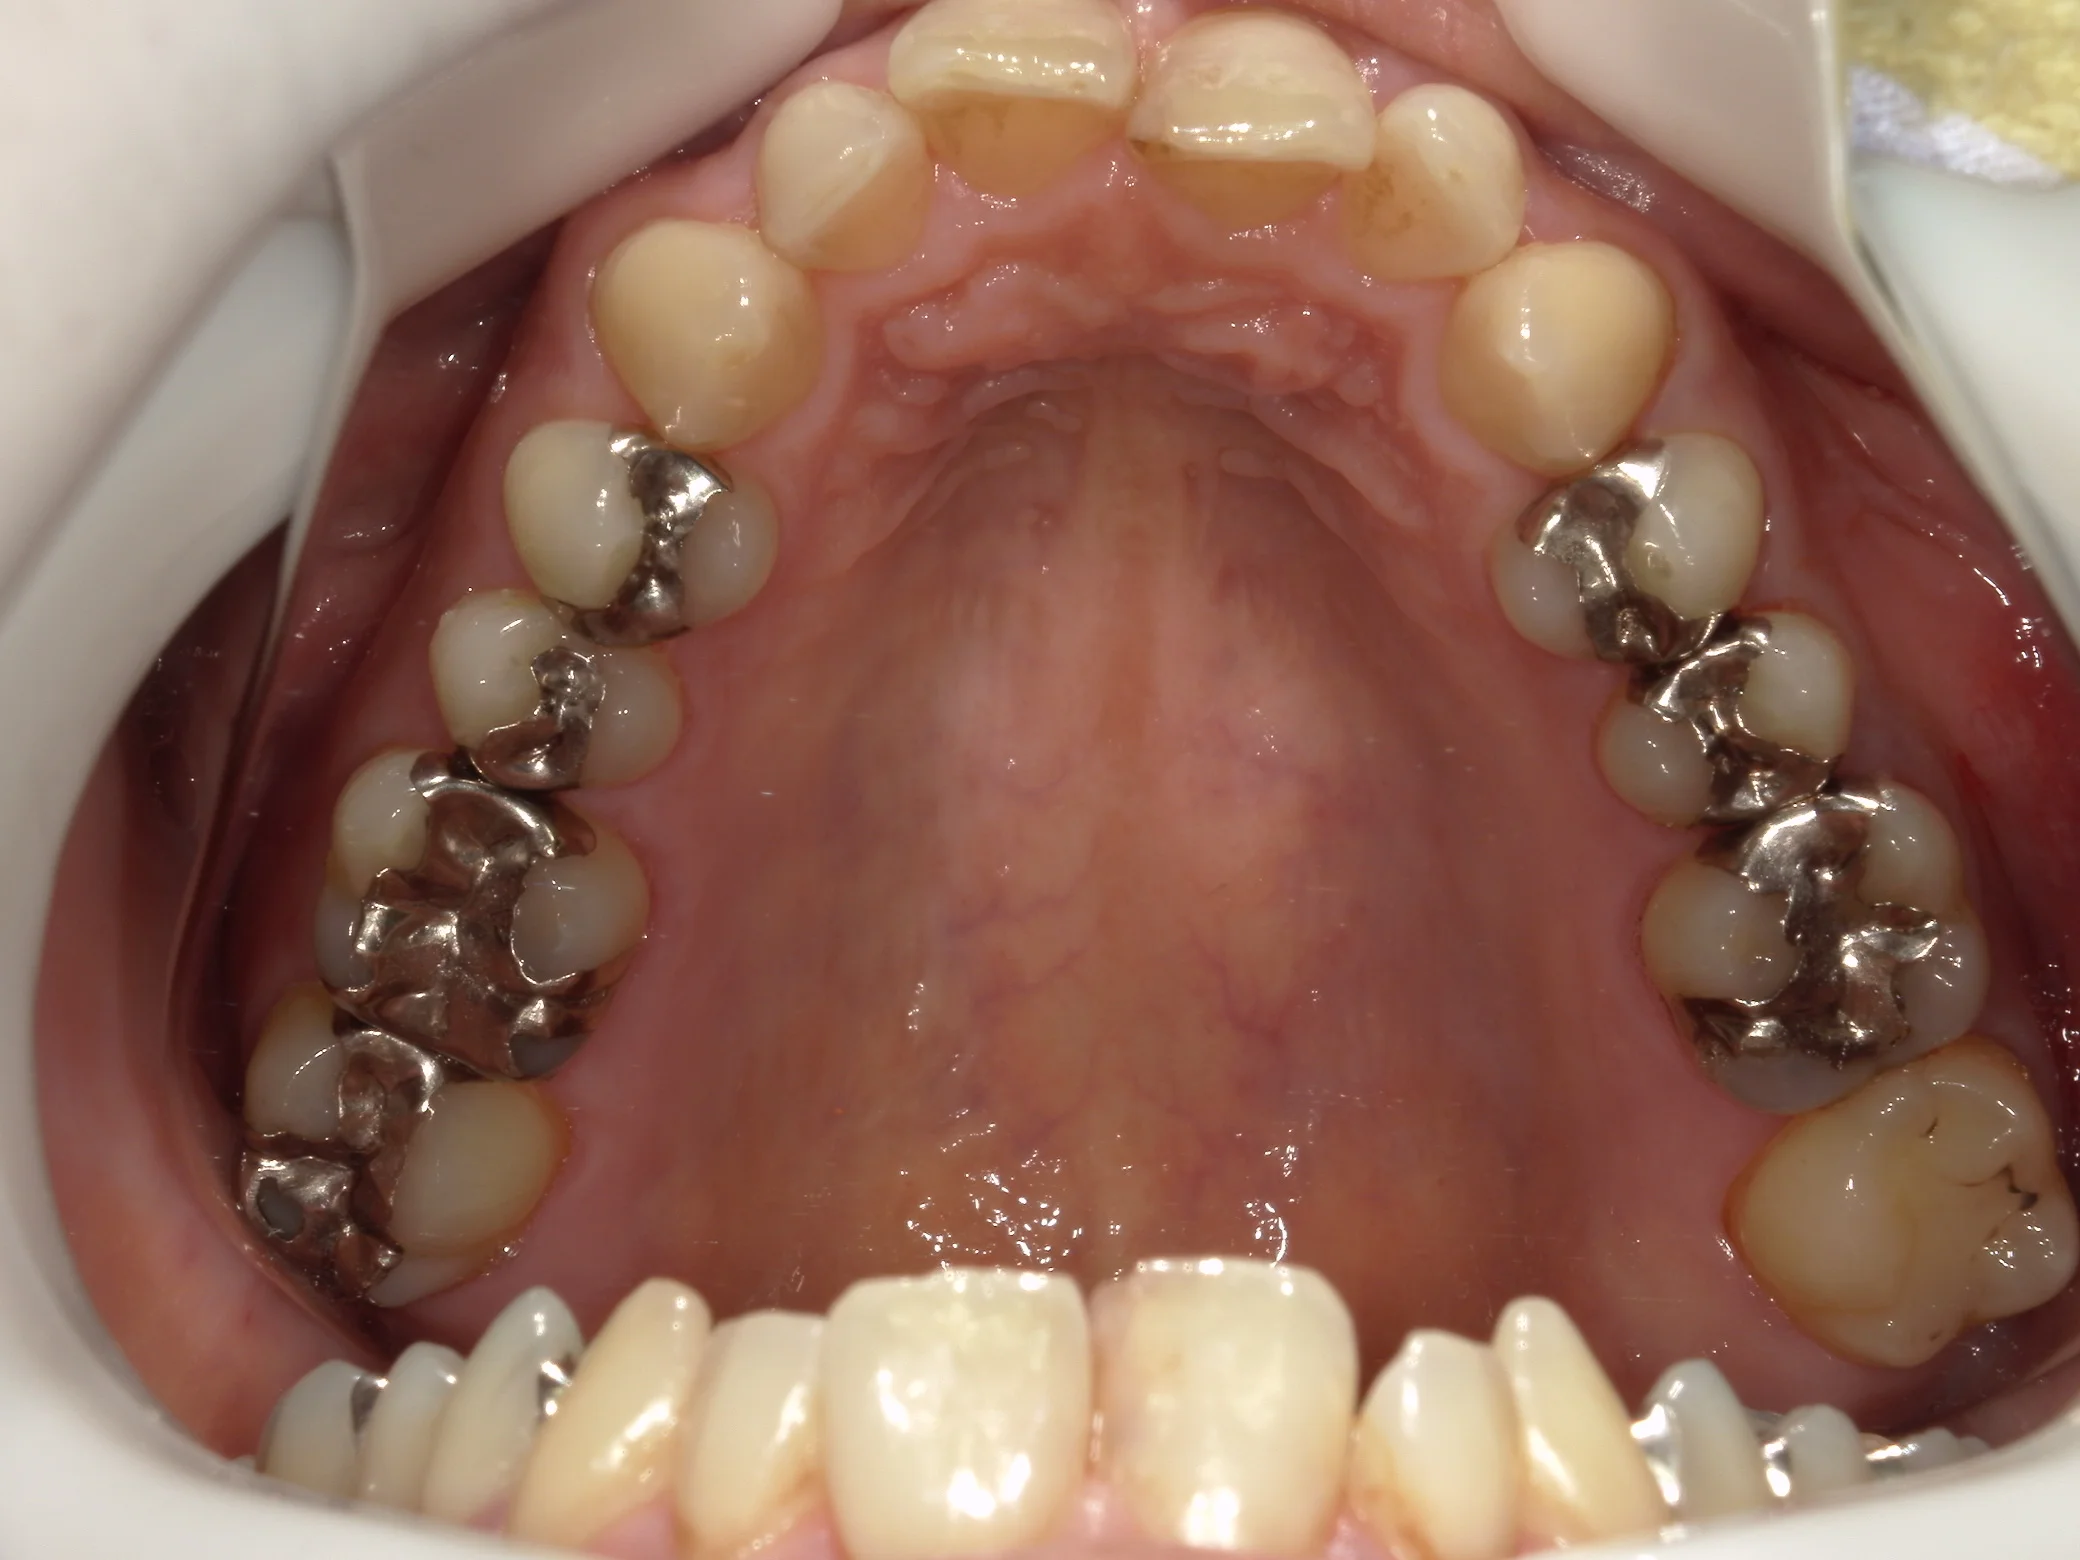

まずは術前ですね。

今回は神奈川県からの来院の為、一気に4本を行っています。

処置を行ったのは金属が入っている3本と、右側一番奥の白い詰め物が入っているところです。